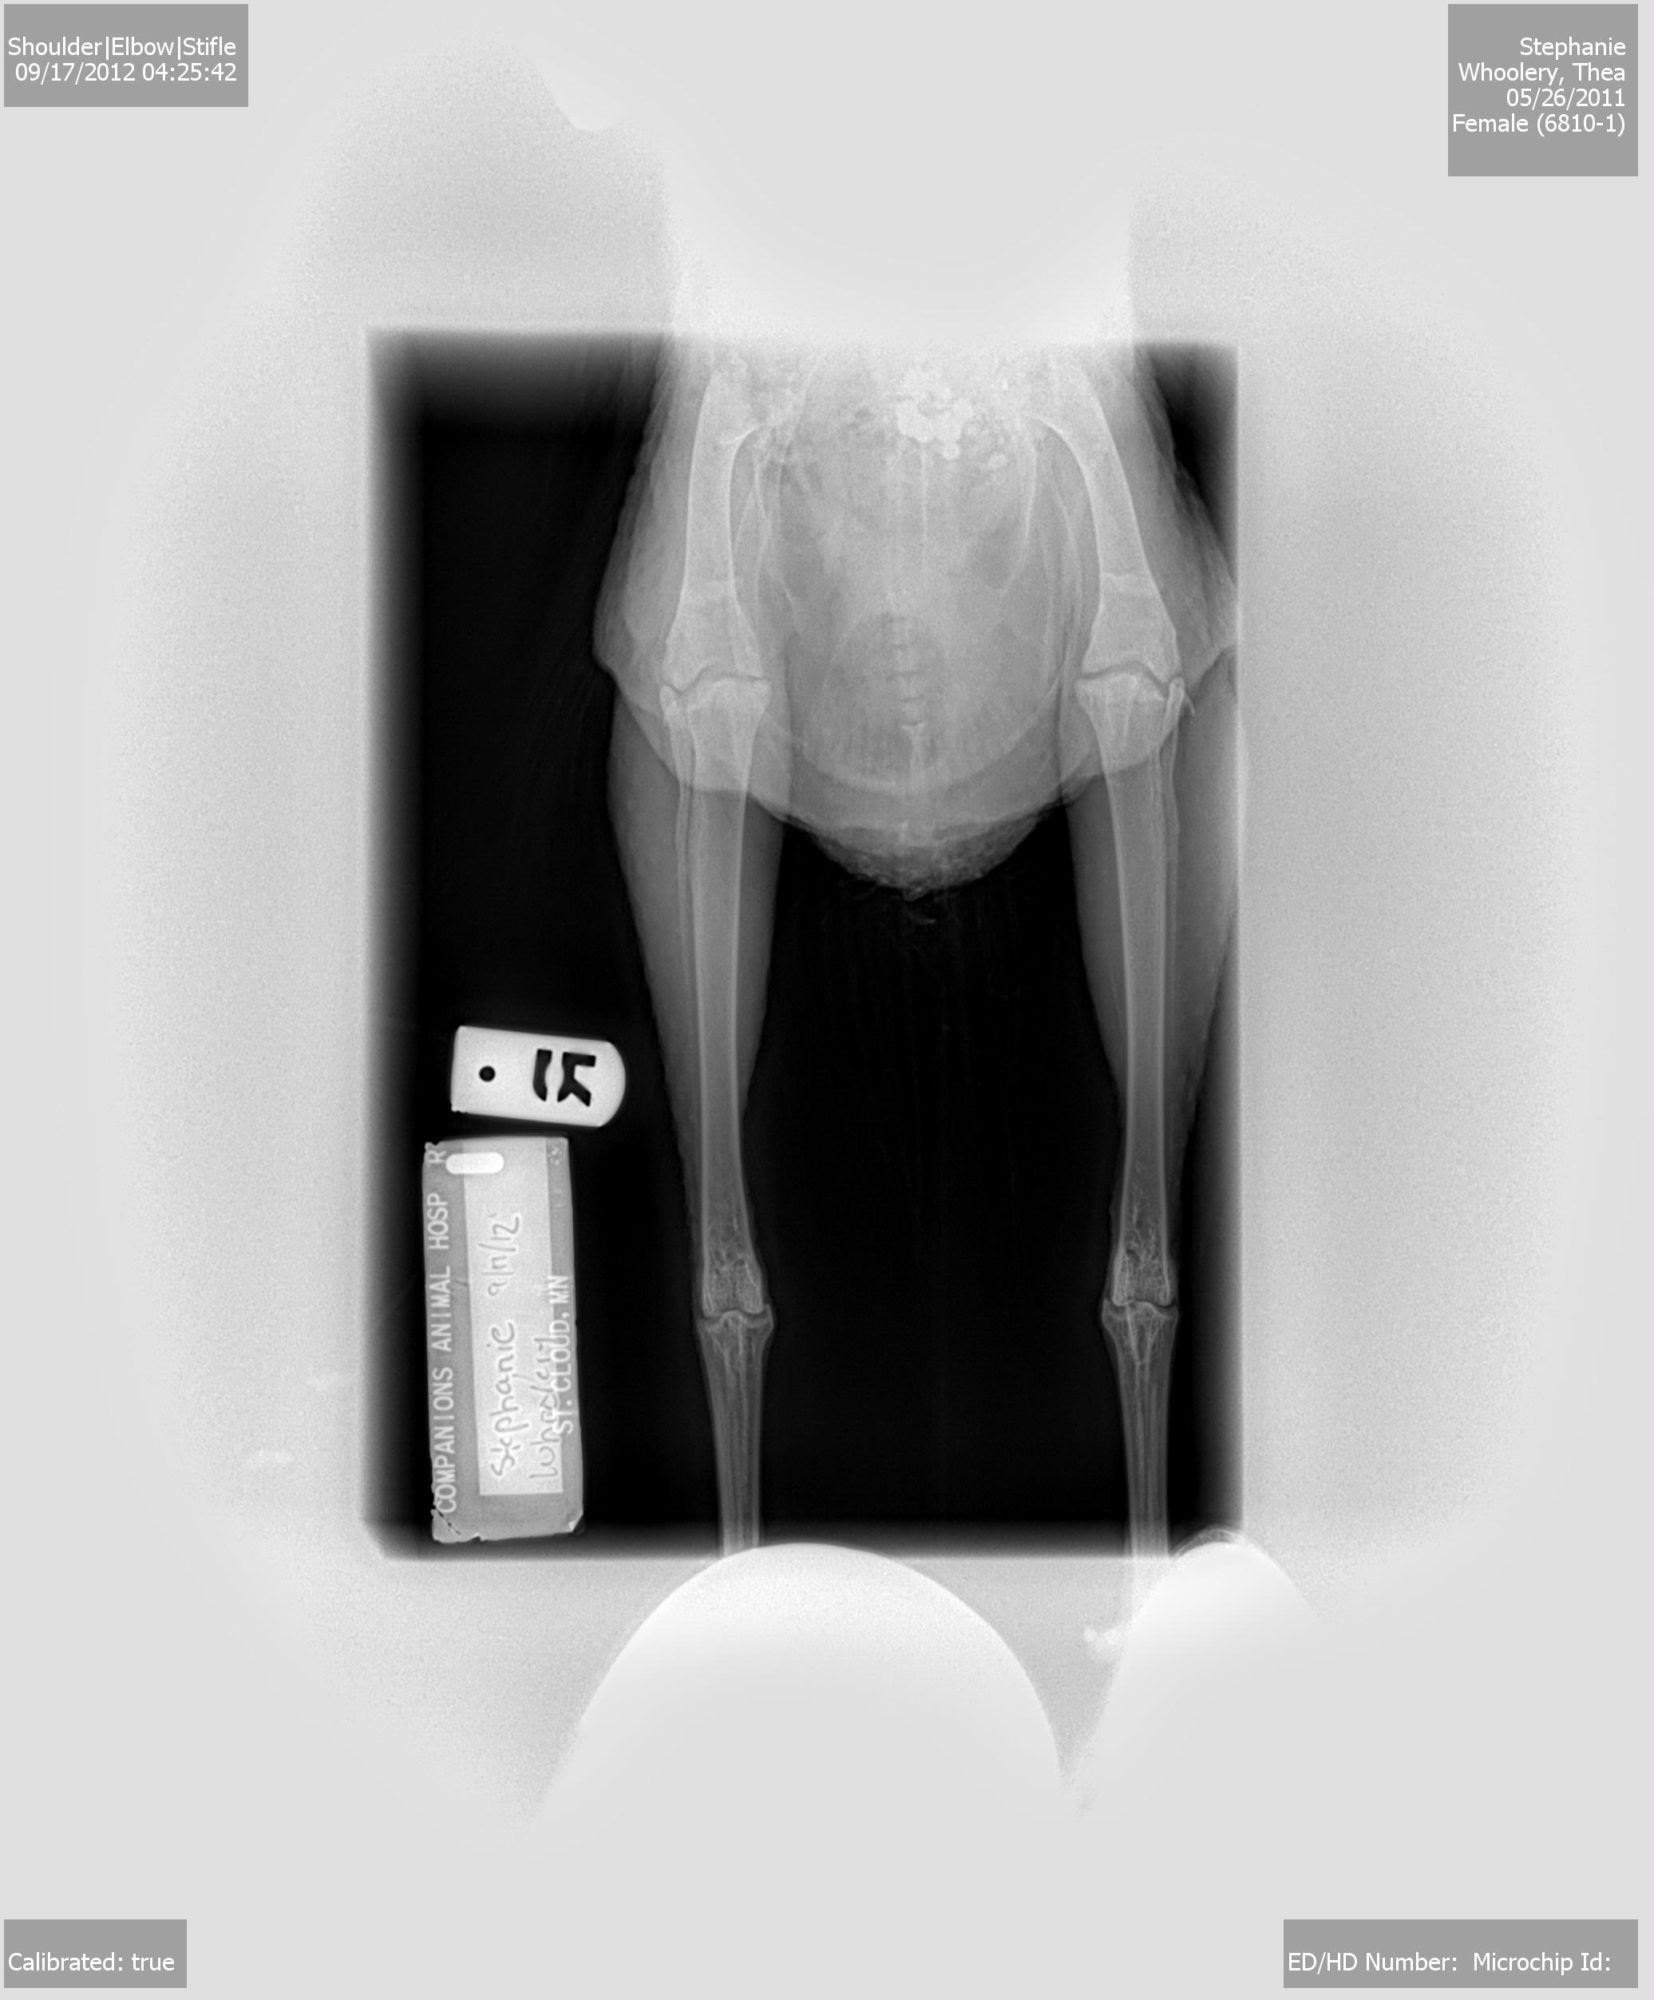

Took some xrays and everything looked good, not even swelling. We did a quick laser therapy session to hopefully help her out (was only like 20 bucks, whatever)

Aww such a sweet girl...she reminds me of my Chicklet. Neat X-rays. Did she say what those bead like things were inside her body...hehe

She asked me the same thing! She said that was the rocks in her gizzard and she wanted to know why the rocks or whatever are so perfect shaped. I thought that was sooo odd. I have no idea.